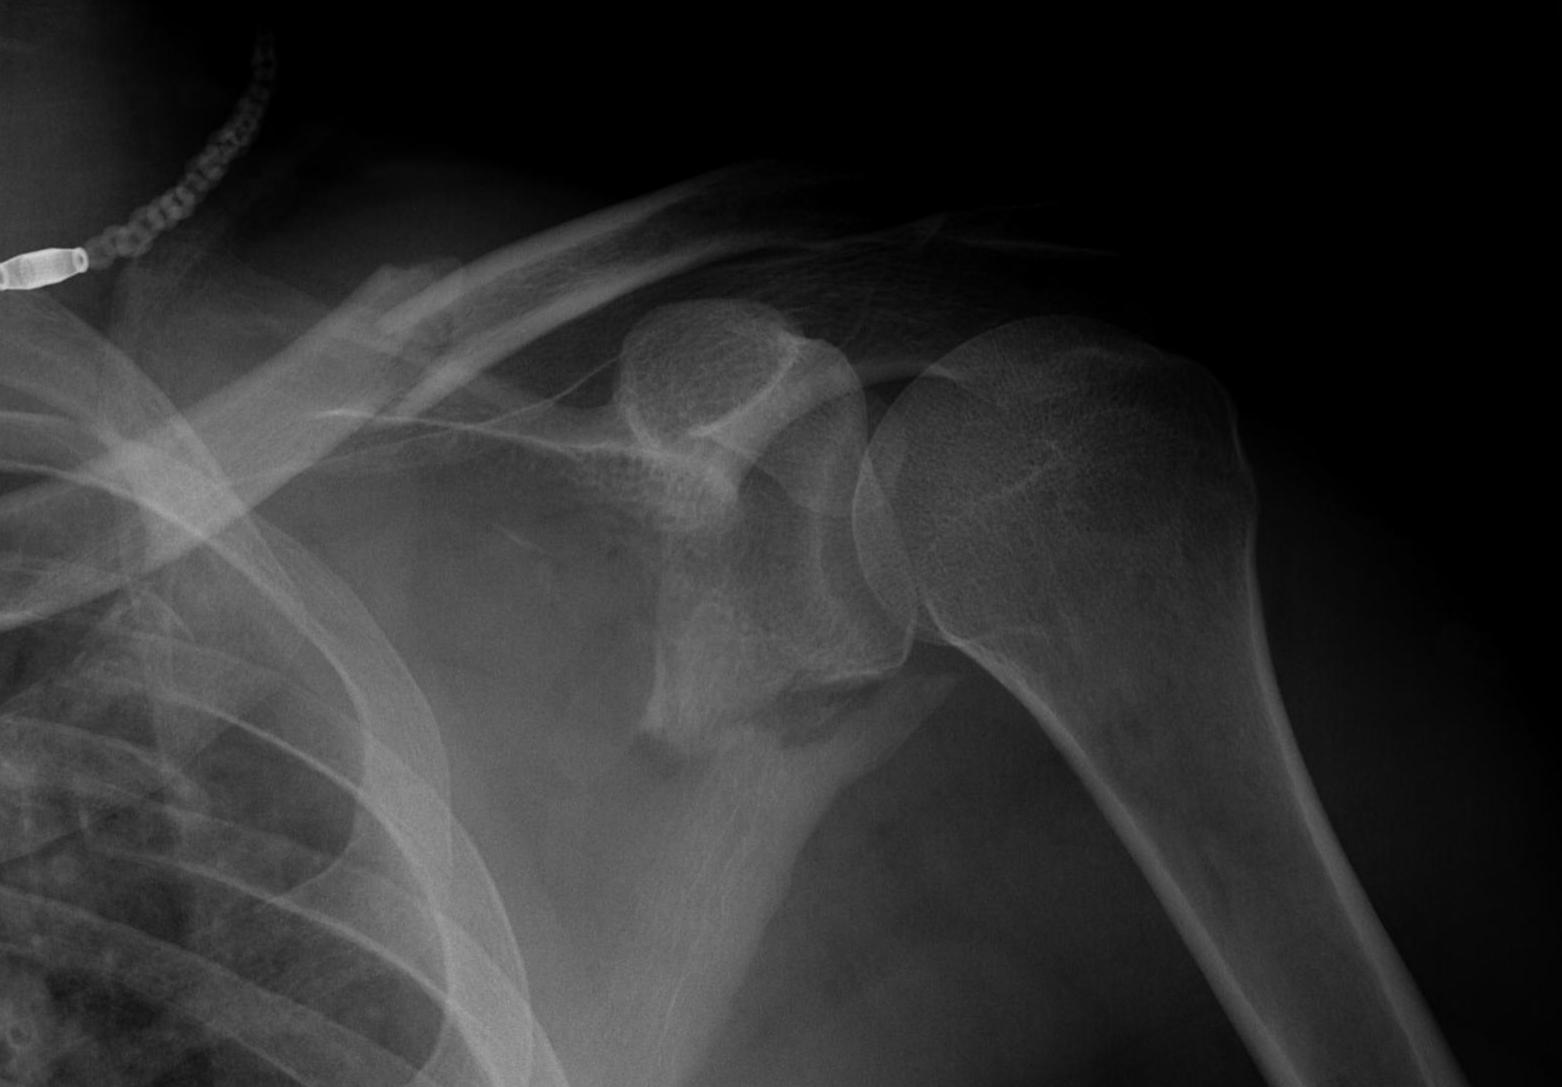

Scapular neck fracture with clavicle fracture

floatfloatfloat